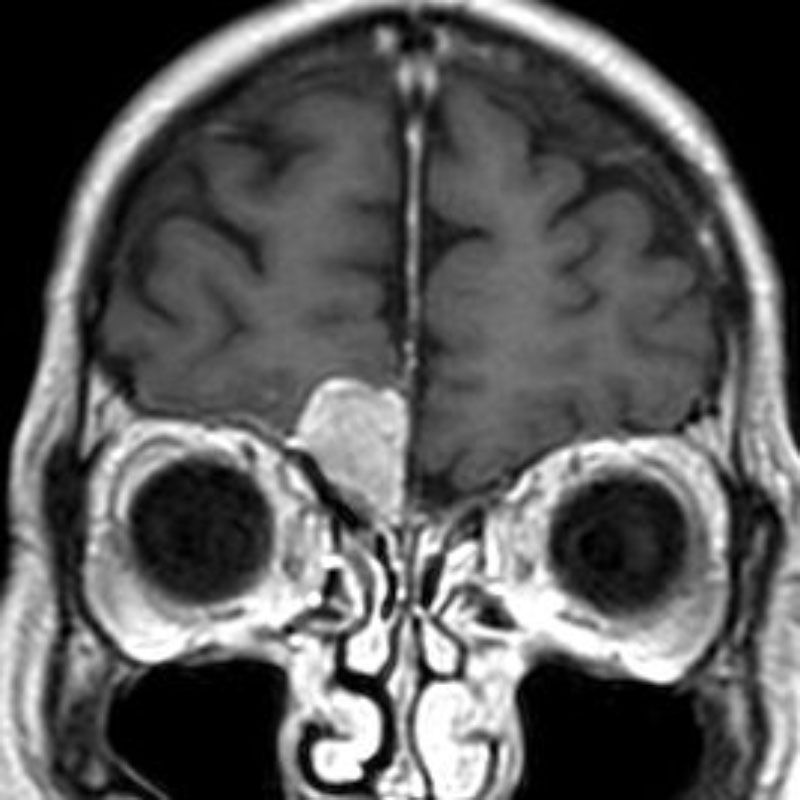

断層撮影

手術前1

手術前2